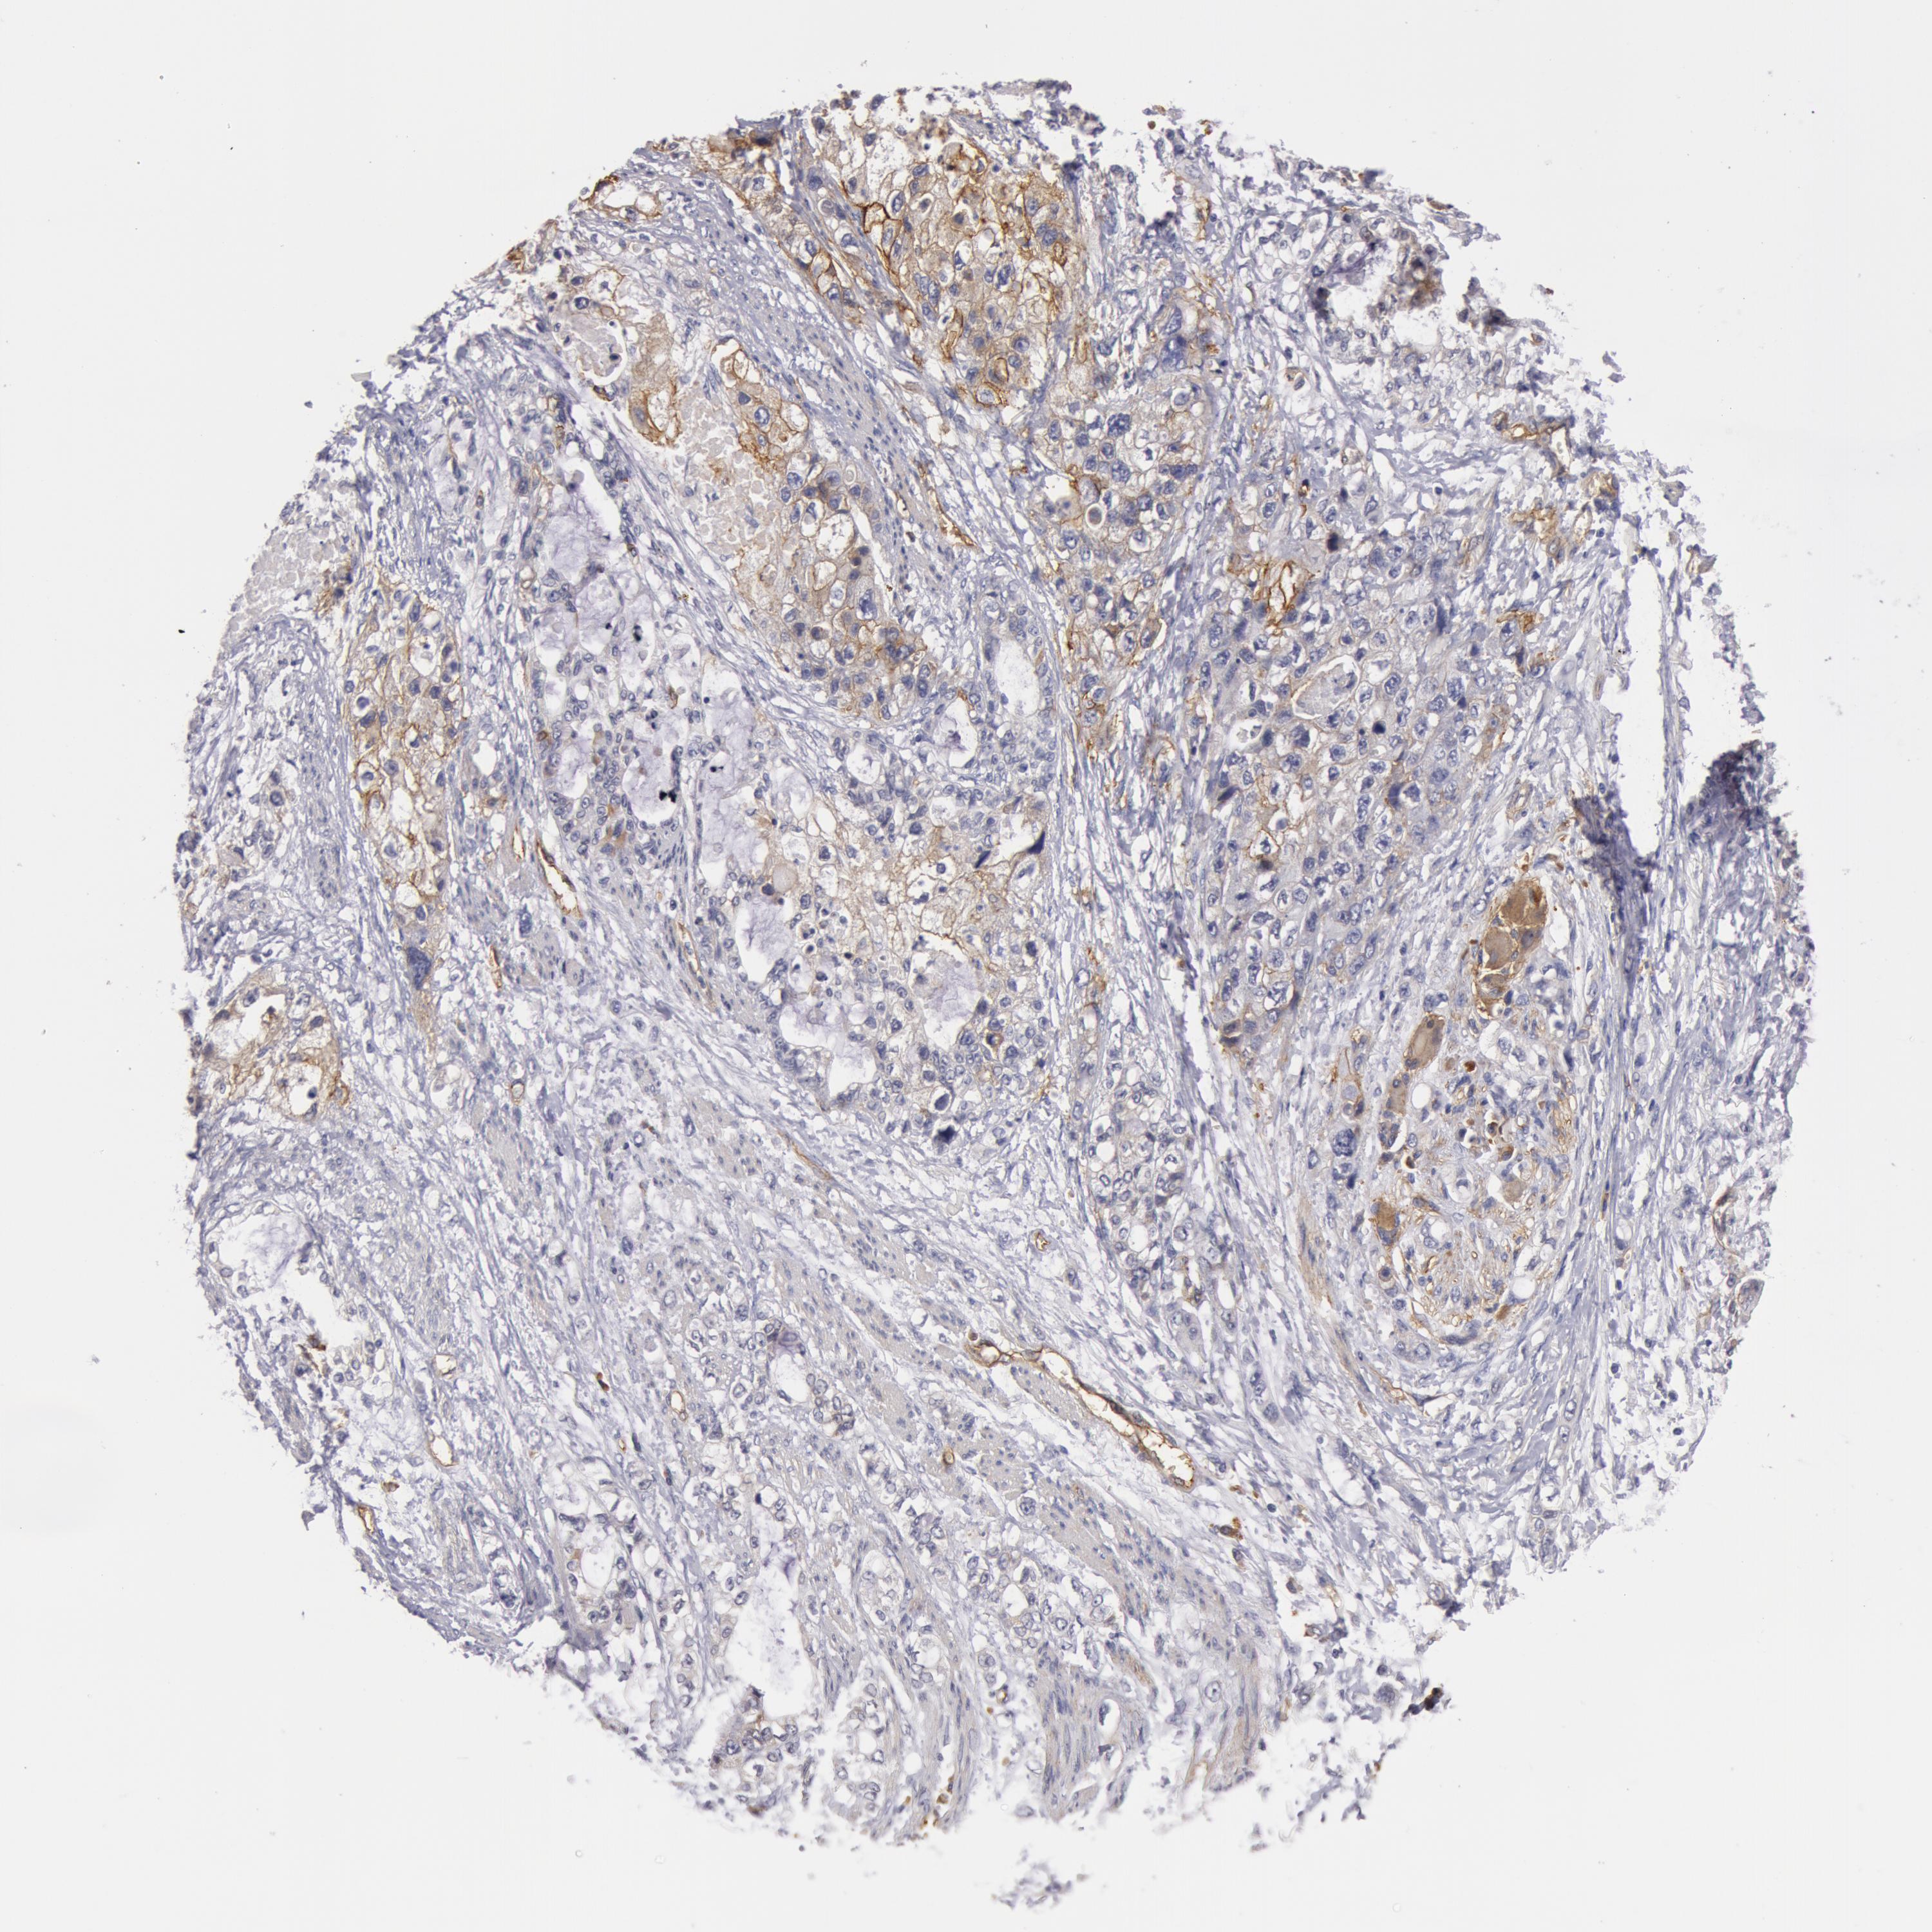

STOMACH CANCER - Protein expressioni

A mouse-over function shows sample information and annotation data. Click on an image to view it in a full screen mode. Samples can be filtered based on level of antibody staining by selecting one or several of the following categories: high, medium, low and not detected. The assay and annotation is described here.

Antibody stainingi

Antibody staining in the annotated cell types in the current human tissue is reported as not detected, low, medium, or high, based on conventional immunohistochemistry profiling in selected tissues. This score is based on the combination of the staining intensity and fraction of stained cells.

Each image is clickable and will lead to virtual microscopy that enables deeper exploration of all samples and also displays staining intensity scores, fraction scores and subcellular localization as well as patient and tissue information for each sample.

Antibody HPA001554

Staining

High

Medium

Low

Not detected

Intensity

Strong

Moderate

Weak

Negative

Quantity

>75%

75%-25%

<25%

None

Location

Nuclear

Cytoplasmic/membranous

Cytoplasmic/membranous,nuclear

Adenocarcinoma, NOS